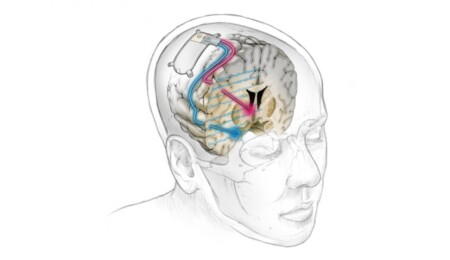

"Sarah" ismini kullanan 36 yaşındaki hastaya uygulanan deneysel cihaz, depresyonla ilişkili beyin aktivitelerini tespit ederek, beynin derinliklerine küçük elektriksel uyarı darbeleri iletiyor ve bu aktiviteleri sona erdiriyor.

Araştırmacılar herkese aynı beyni uyarma tedavisini uygulamak yerine, Sarah'nın depresyonunun beyinde hangi noktaya karşılık geldiğini manuel olarak gözlemledi.

Bunun sonucunda majör depresyonla bağlantılı, yeni beyin dalgaları tanımlandı. Biyobelirteç diye nitelenen bu sinyaller, cihazın kişiselleştirilmesinde kullanıldı.

Semptomların giderilmesi için en iyi yerin anlaşılması biraz zaman aldı ama elektrok uygun bölgeye yerleştirildiğinde 6 saniye boyunca küçük bir miktar elektrik üretmeyi başardı.